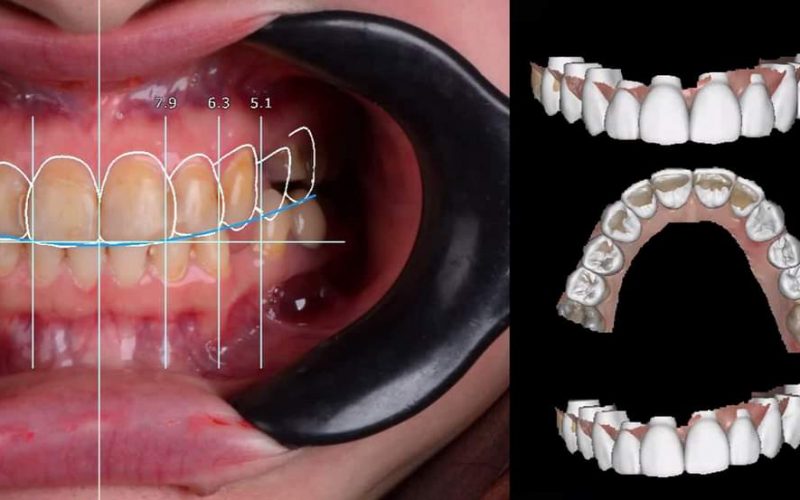

Gallery

Advanced Technology

A fully digital CAD/CAM System that streamlines the design and fabrication process for unmatched quality and consistency.